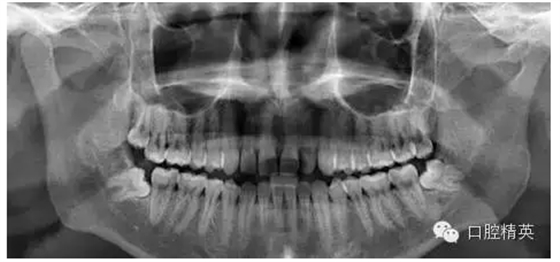

1、拔除前口內(nèi)全景片

7、拔牙后全景片